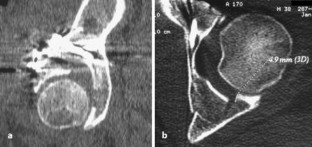

Vordere Pfeilerfraktur des Acetabulums mit dorsaler Impression

Anterior column fracture of the acetabulum with dorsal impression

Es wird ein ungewöhnlicher Fall einer vorderen Pfeilerfraktur des Acetabulums mit ausgedehnter Impression im Bereich des hinteren Pfeilers beschrieben. Nach primärer Osteosynthese über einen ilioinguinalen Zugang erfolgt die Reposition der dorsalen Impressionen über einen hinteren Zugang mit Repositionskontrolle mittels chirurgischer Hütluxation.

An unusual case of an anterior column fracture of the acetabulum with extended marginal impaction at the posterior column is presented. Fracture fixation was primarily performed by an ilioinguinal approach followed by a posterior approach with surgical dislocation of the hip to reduce the impacted fragments.